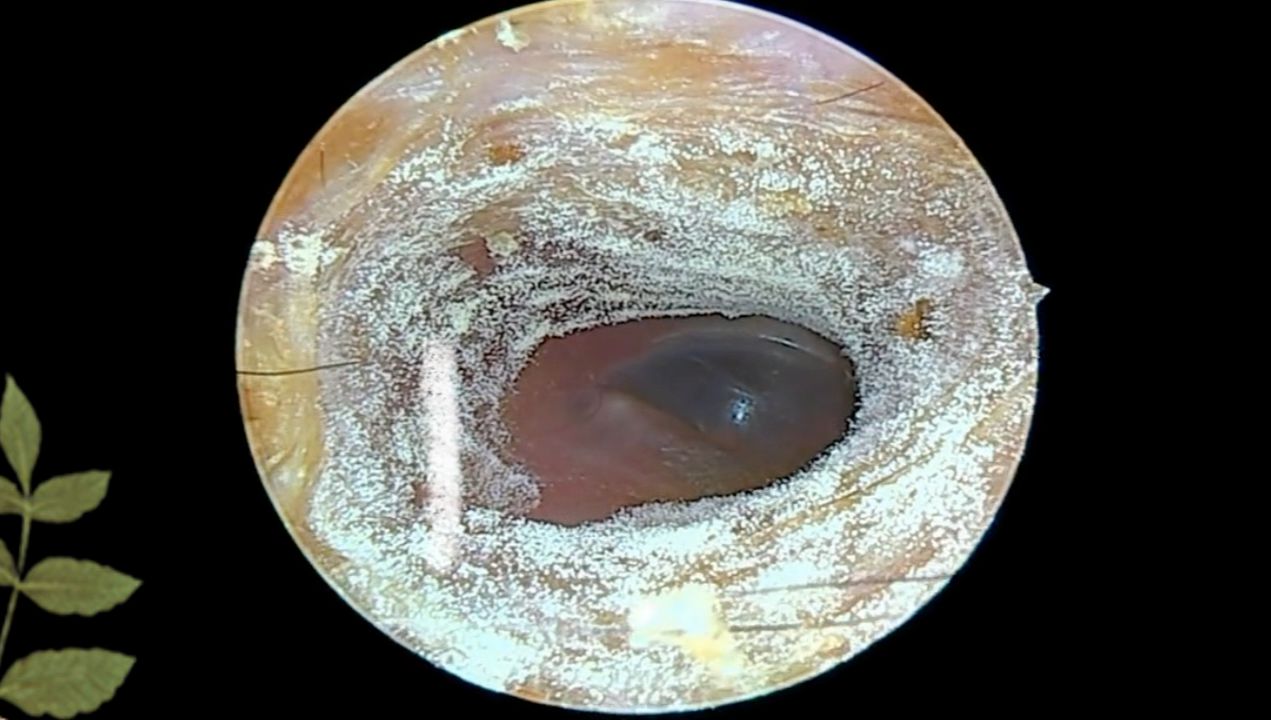

耳朵里好厚一层霉菌厚干片 !

图片尺寸1271x720